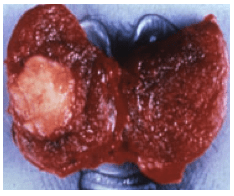

La cause la plus fréquente (85%) est la transformation d’une ou plusieurs glandes parathyroïdes en un adénome, qui sécrète de la parathormone en excès. Il n’y a pas, à ce jour, de cause, ni de facteur de risque connue pour expliquer cette évolution spontanée et isolée.

Le traitement de référence est chirurgical. Il consiste à retirer, la ou les glandes parathyroïdes hyperfonctionnelles, par une incision réalisée à la partie base du cou.

L’hyperparathyroïdie primaire

Il s’agit d’une production anormalement élevée d’hormone parathyroïdienne, appelée parathormone (PTH), par les glandes parathyroïdes. Cette élévation de la parathormone est à l’origine d’une augmentation du taux de calcium dans le sang (hypercalcémie) par une augmentation de la résorption osseuse, par la réduction de l’élimination rénale du calcium et par l’augmentation de l’absorption intestinale de calcium.